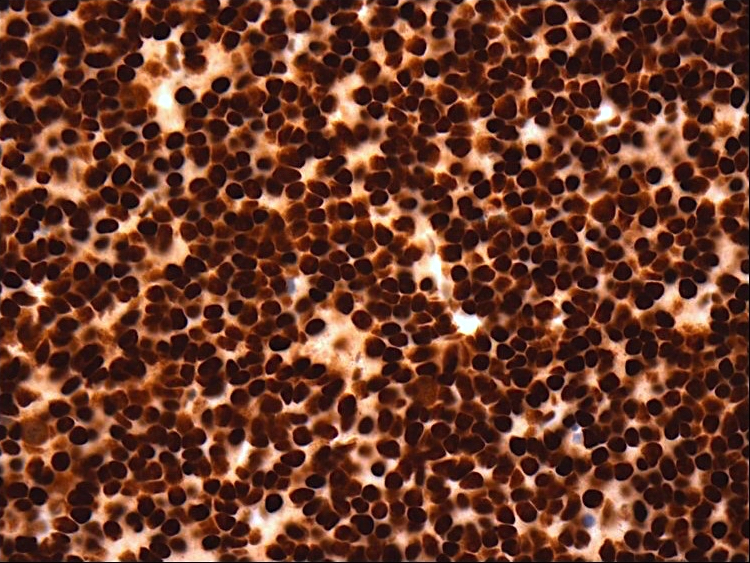

Positive stains

- Ki67:

- Grade 2 tumors: usually < 5% of tumor nuclei

- Grade 3 tumors: generally > 10% of tumor nuclei (Neuro Oncol 2014;16:1244, Neuro Oncol 2016;18:888)